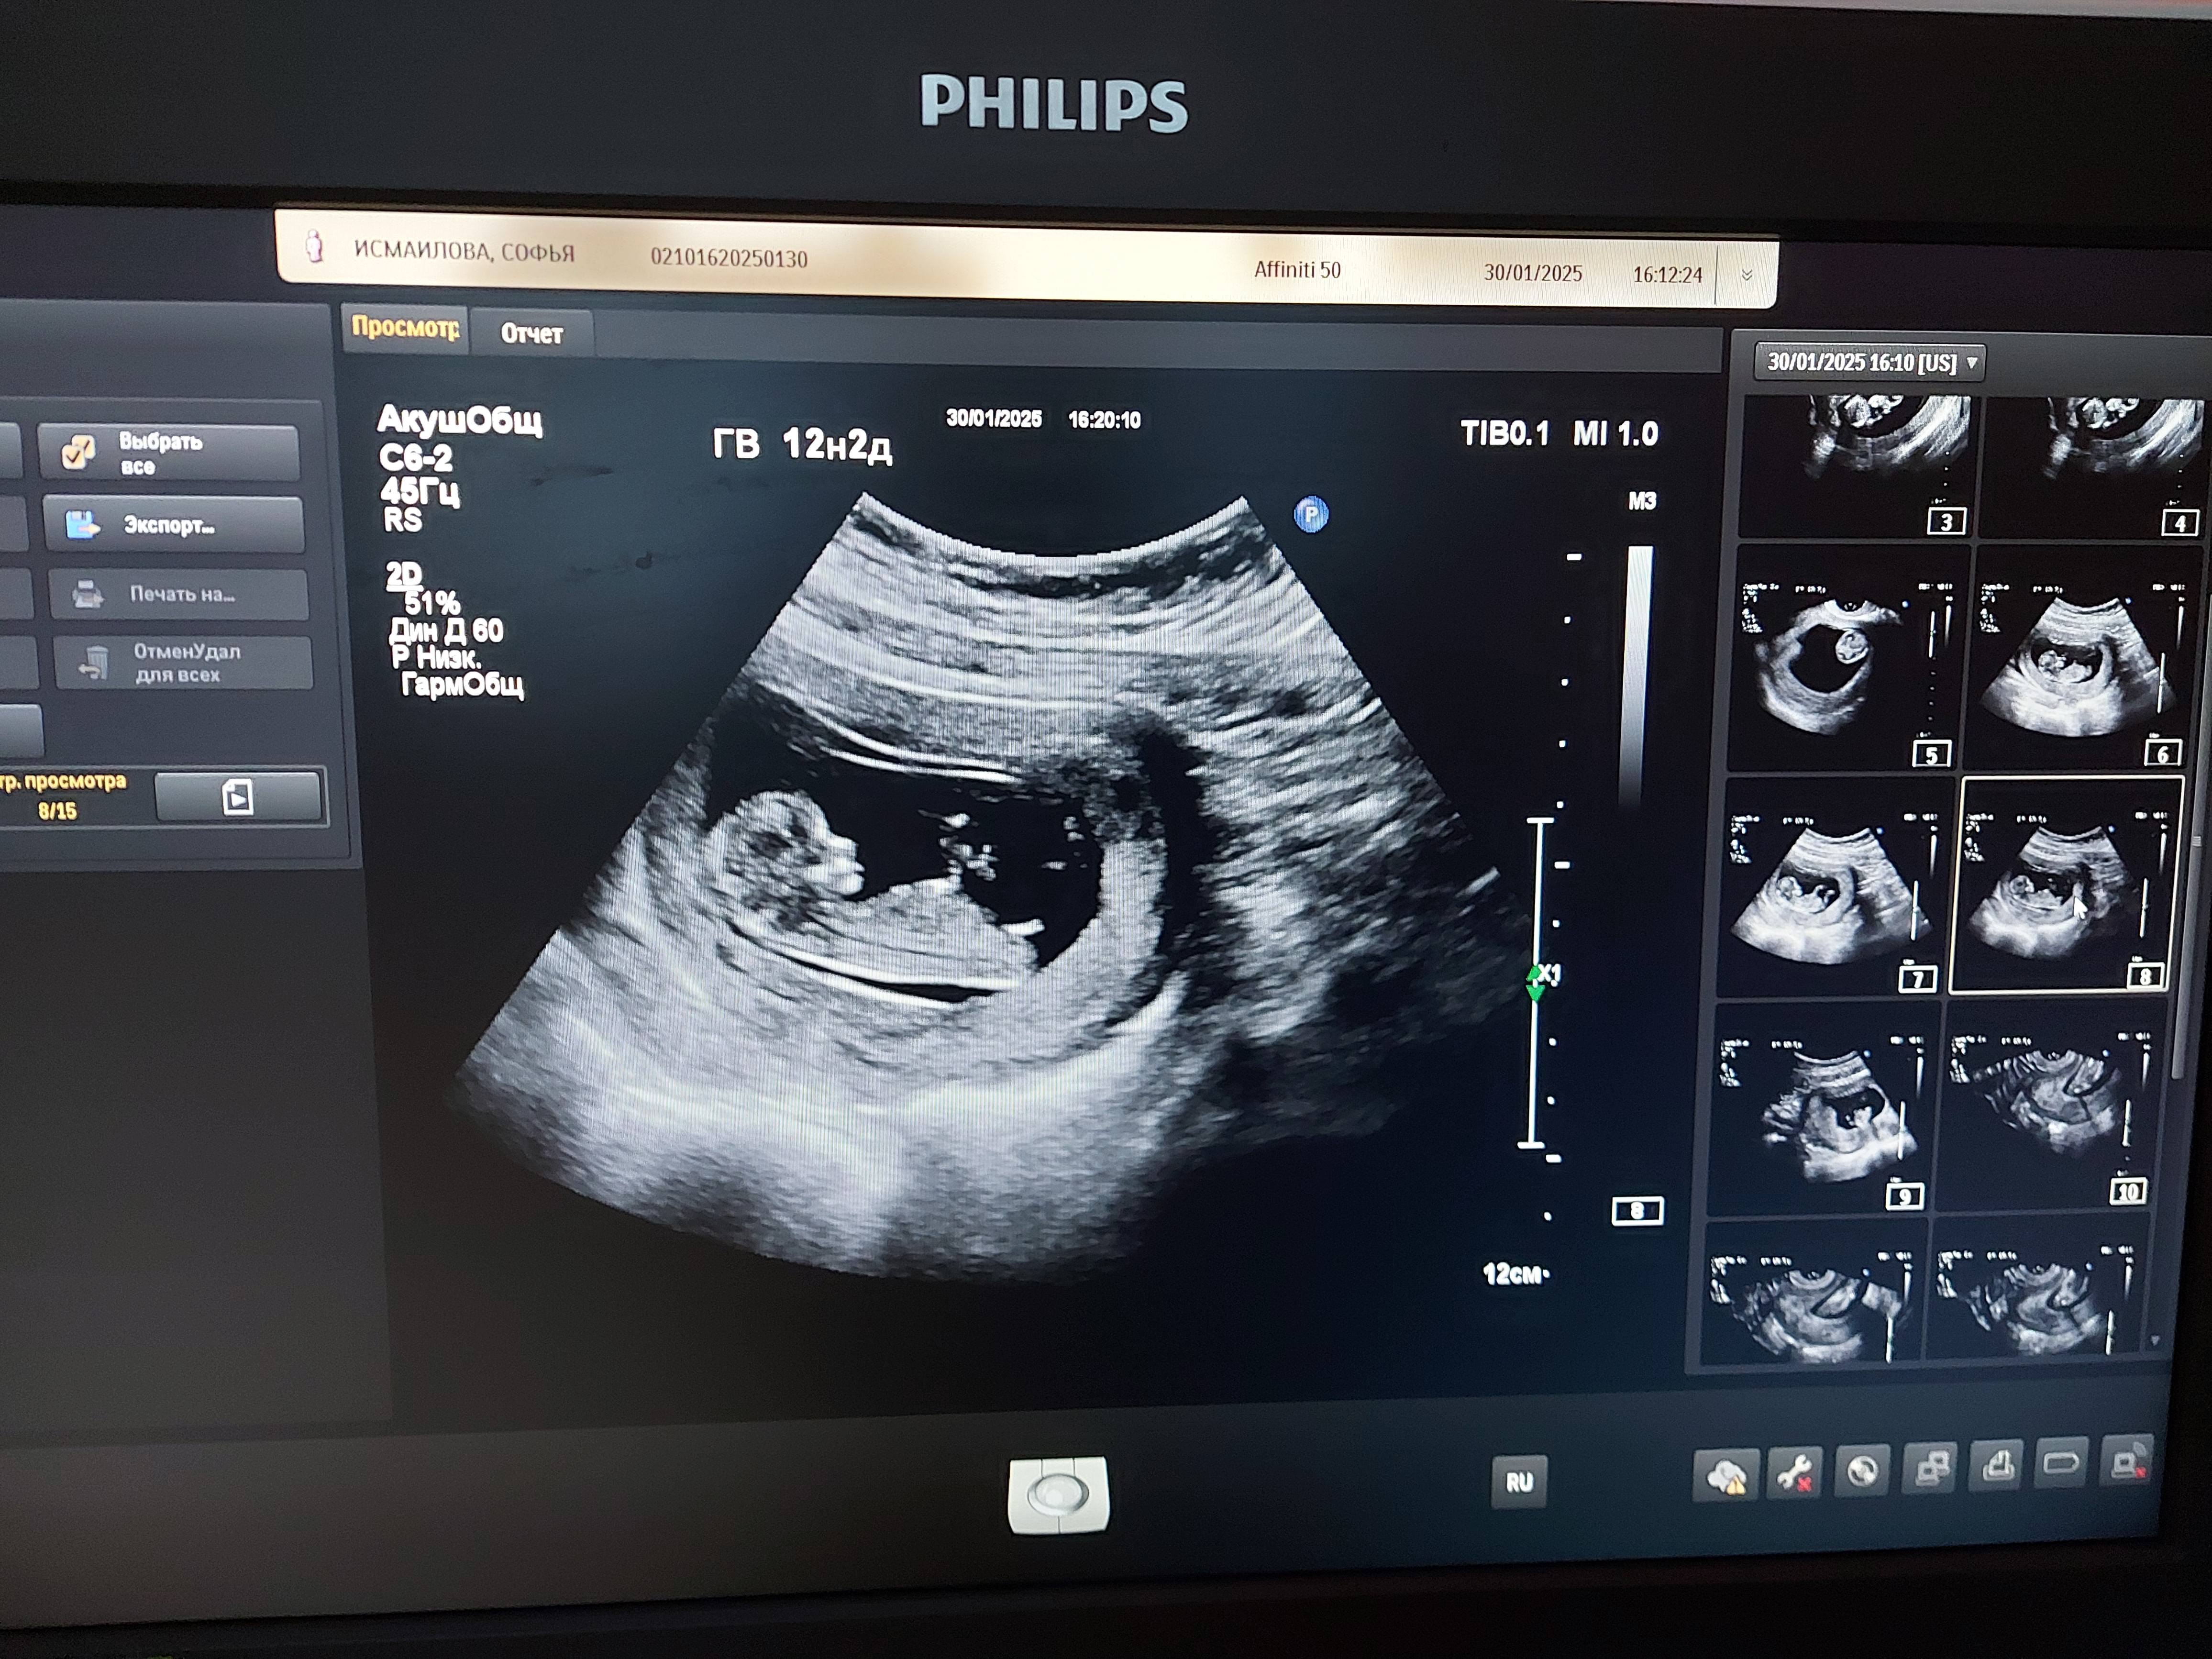

Мальчик или девочка

Вроде и угол не большой, можно было девочку увидеть, но мне, по расположению писюнчика относительно мочевого пузыря (если это точно он на снимке😅), кажется, что мальчик🩵

Мне кажется, что мальчик

Думаю, что мальчик у вас💙

Мальчик явно 💙

Малышарик прячется Определение пола на 15 неделе